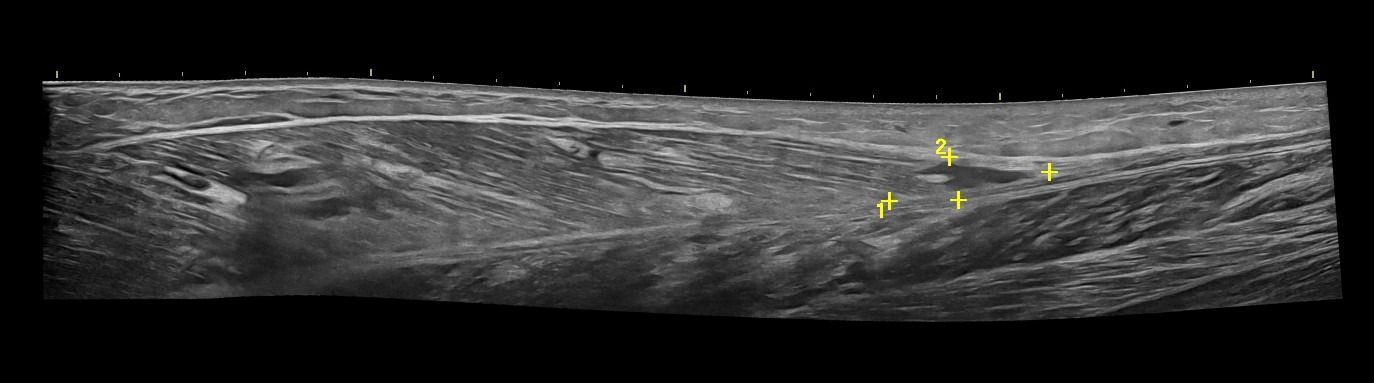

- Κατηγοριοποίηση (Grading) Θλάσεων Μυών: Το Υπερηχογράφημα Μυών μπορεί να αποτελέσει ιδανικό εργαλείο για την ανίχνευση και εκτίμηση της έκτασης μυϊκών θλάσεων μετά από τραυματισμό ή άλλα μυϊκά προβλήματα.

- Διάγνωση Μυϊκών Βλαβών: Το Υπερηχογράφημα Μυών επιτρέπει την αναγνώριση μυϊκών παθήσεων όπως τα αιματώματα, τα λιπώματα, τα νεοπλάσματα και η σημειολογία ασβεστοποιού μυοσίτιδας.